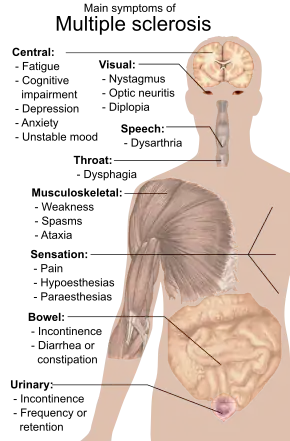

As MS lesions can affect any part of the central nervous system, A person with MS can have almost any neurological symptom or sign referable to the central nervous system.

Fatigue is one of the most common symptoms of MS.[26] Autonomic, visual, motor, and sensory problems are also among the most common.[1]

The specific symptoms are determined by the locations of the lesions within the nervous system, and may include focal loss of sensitivity and/or changes in sensation in the limbs, such as feeling tingling, pins and needles, or numbness; limb motor weakness/pain, blurred vision,[27] pronounced reflexes, muscle spasms, difficulty with ambulation, difficulties with coordination and balance (ataxia); problems with speech or swallowing, visual problems (optic neuritis manifesting as eye pain & vision loss,[28] or nystagmus manifesting as double vision), fatigue, and bladder and bowel difficulties (such as urinary and/or fecal incontinence or retention), among others.[1] When multiple sclerosis is more advanced, walking difficulties can occur and the risk of falling increases.[29][19][30]

Difficulties thinking and emotional problems such as depression or unstable mood are also common.[1] The primary deficit in cognitive function that people with MS experience is slowed information-processing speed, with memory also commonly affected, and executive function less commonly. Intelligence, language, and semantic memory are usually preserved, and the level of cognitive impairment varies considerably between people with MS.[31][32][33]

Uhthoff's phenomenon, a worsening of symptoms due to exposure to higher-than-usual temperatures, and Lhermitte's sign, an electrical sensation that runs down the back when bending the neck, are particularly characteristic of MS, although may not always be present.[1] Another presenting manifestation that is rare but highly suggestive of a demyelinating process such as MS is bilateral internuclear ophthalmoplegia, where the patient experiences double vision when attempting to move their gaze to the right & left.[34]